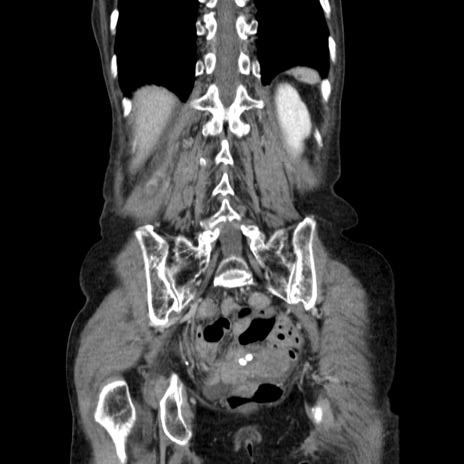

横断像

【症例】80歳代女性

【主訴】胸のつかえ感

【現病歴】約9時間前に食後から胸のつかえた感じあり、嘔吐あり、来院。

【既往歴】胃癌(全摘)、胆摘、虫垂炎

【身体所見】心窩部に圧痛あり、反跳痛なし。

【データ】WBC 5700、CRP 0.05